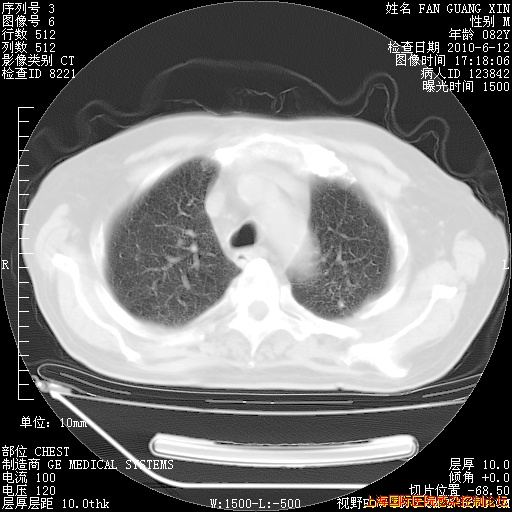

补发6月12日肺部CT肺窗

6月12日肺窗

整整相隔30天的肺部CT好像有所好转啊。甲强龙减量第3天,需要观察体温。